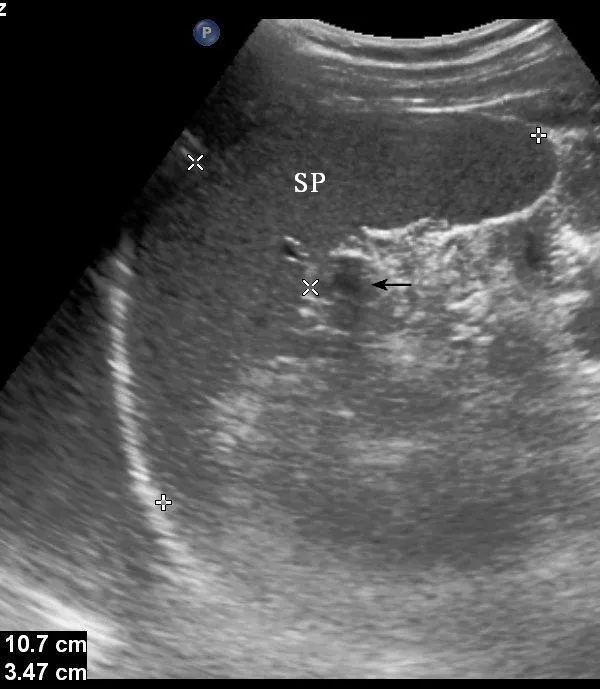

灰阶超声,副脾,显示脾门处一圆形回声与脾回声类似的副脾(箭头所示)

SP:脾脏